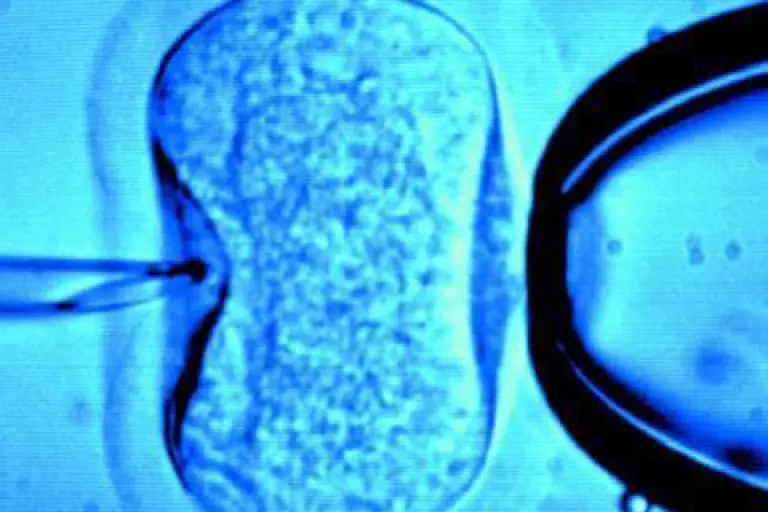

Se busca reformar diversas disposiciones de la ley General de Salud para garantizar el derecho a la libertad reproductiva.

La bancada del PRD en el Senado propuso reformas a la Ley General de Salud, para brindar seguridad jurídica a quienes utilicen el método de reproducción asistida.